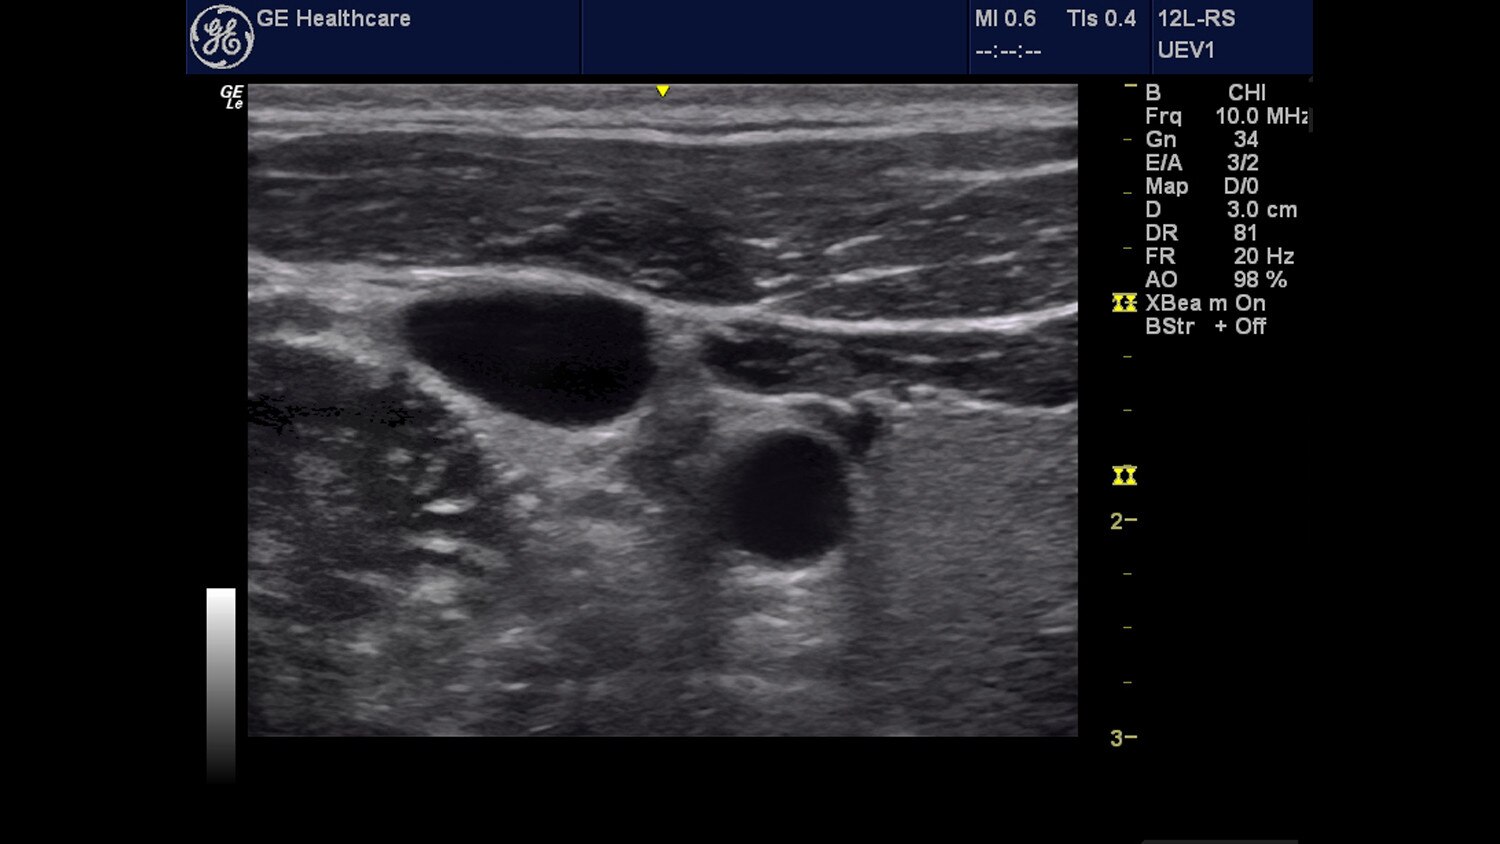

Venue™ Point of Care Ultrasound

Designed for simplicity, speed, and precision, Venue is the premier solution of our point of care ultrasound systems.